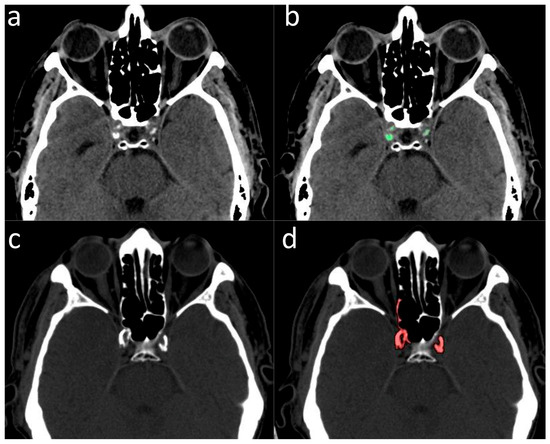

2.2. Validation of ICA Calcium Score as Surrogate Marker of CACs